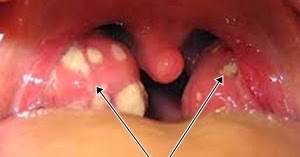

Radang Amandel (Tonsilitis): Ciri, Gejala, Penyebab, & Cara Mengobati

Radang Amandel (Tonsilitis): Ciri, Gejala, Penyebab, & Cara MengobatiCara menghilangkan radang amandel dengan cepat

Gejala Dan Cara Mengobati Amandel Tanpa Operasi Yang Alami

Gejala dan Cara Mengobati Amandel Tanpa Operasi yang AlamiCara mengobati amandel dengan cepat secara alami